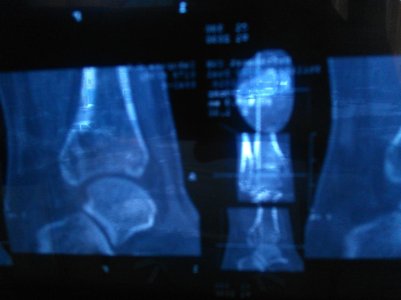

6 января на МРТ выявили перелом (фото№ 1).

Заключение: МР-признаки перелома заднего края большеберцовой кости; МР-признаки артрозных проявлений в левом голеностопном тарано-ладьевидном и таранно- пяточном суставах.

26января на КТ заключение: несросшийся перелом заднего края большеберцовой кости левого голеностопа.